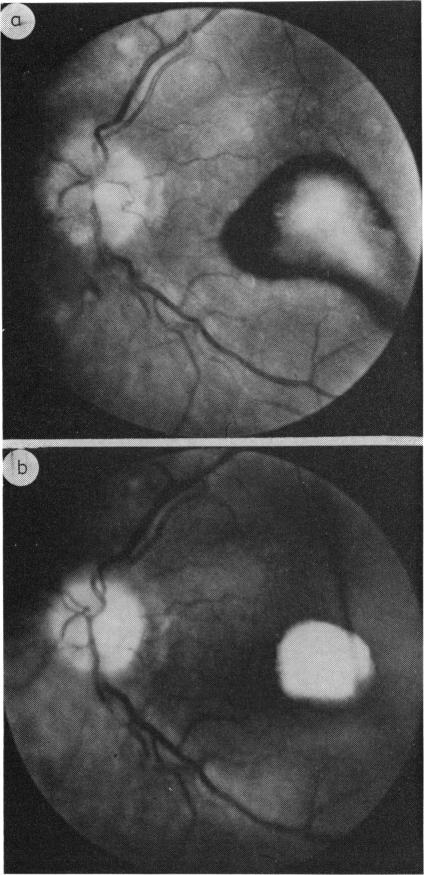

Macular changes resulting from papilloedema.

Six cases are presented with macular changes in association with papilloedema; 4 suffered permanent visual loss. The present paper emphasises this previously infrequent finding and discusses the haemodynamic and mechanical factors responsible. The macular changes consisted of haemorrhages situated in front, within, or behind the retina, and occasionally the results of neovascular membrane formation produced secondary visual loss. Changes in the pigment epithelium were seen in 3 cases associated with choroidal folds. Macular stars rarely produce visual loss. Recognition of these changes is important in the assessment of the visual loss in papilloedema.